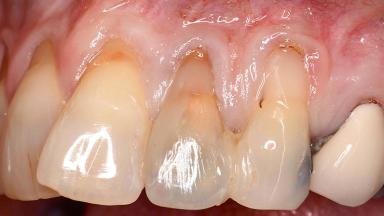

Early Implant Placement, Contour Augmentation, and Autologous Connective-Tissue Graft Using a Tunneling Technique to Replace an Upper Incisor with Generalized Gingival Recession

Variations in soft-tissue volume, evidenced either by an overabundance (Evian and coworkers 1993; Levine and McGuire1997; Dolt and Robbins 1997) or by a deficiency of soft or hard tissue can complicate implant-supported rehabilitations in the esthetic zone (Lorenzana 2008; Lorenzana and coworkers 2009). The present case illustrates the replacement of a failing upper left lateral incisor complicated by generalized severe gingival recession in the esthetic zone.

Soft Tissue Anatomy Intact Defective

Soft Tissue Contour and Volume Significantly deficient